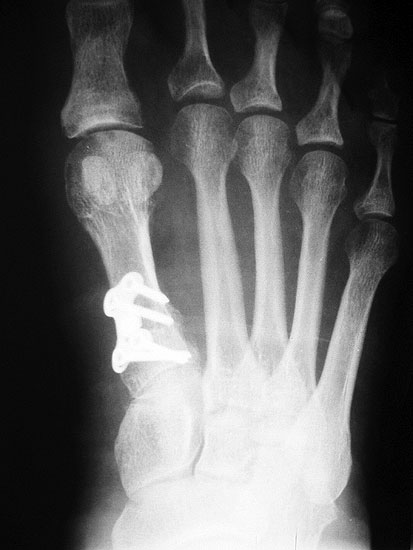

Beim Follow up nach 6 Monaten zeigte sich eine Korrektur des ersten Intermetatarsalwinkels (IMW) um durchschnittlich 9° (Range 4-15°) auf Normwerte (6,8° SD 1,3) (Abb. 21).

Gutes postoperatives Ergebnis mit physiologischem Intermetatarsale I-II Winkel nach open wedge Osteotomie.

Abbildung 21

In zwei Fällen kam es intraoperativ zu einem Bruch der lateralen Kortikalis. In einem Fall konnte durch die winkelstabile Platte eine ausreichende Stabilität erzielt werden, in dem anderen Fall wurde zusätzlich ein perkutaner Kirschnerdraht eingebracht, der nach 6 Wochen entfernt wurde. Eine stabile knöcherne Konsolidierung der Osteotomie ohne Korrekturverlust konnte in beiden Fällen erreicht werden. Die Analyse der Röntgenaufnahmen ergab eine Verlängerung des Os metatarsale I von durchschnittlich 1,8 mm (Range 1-4 mm).